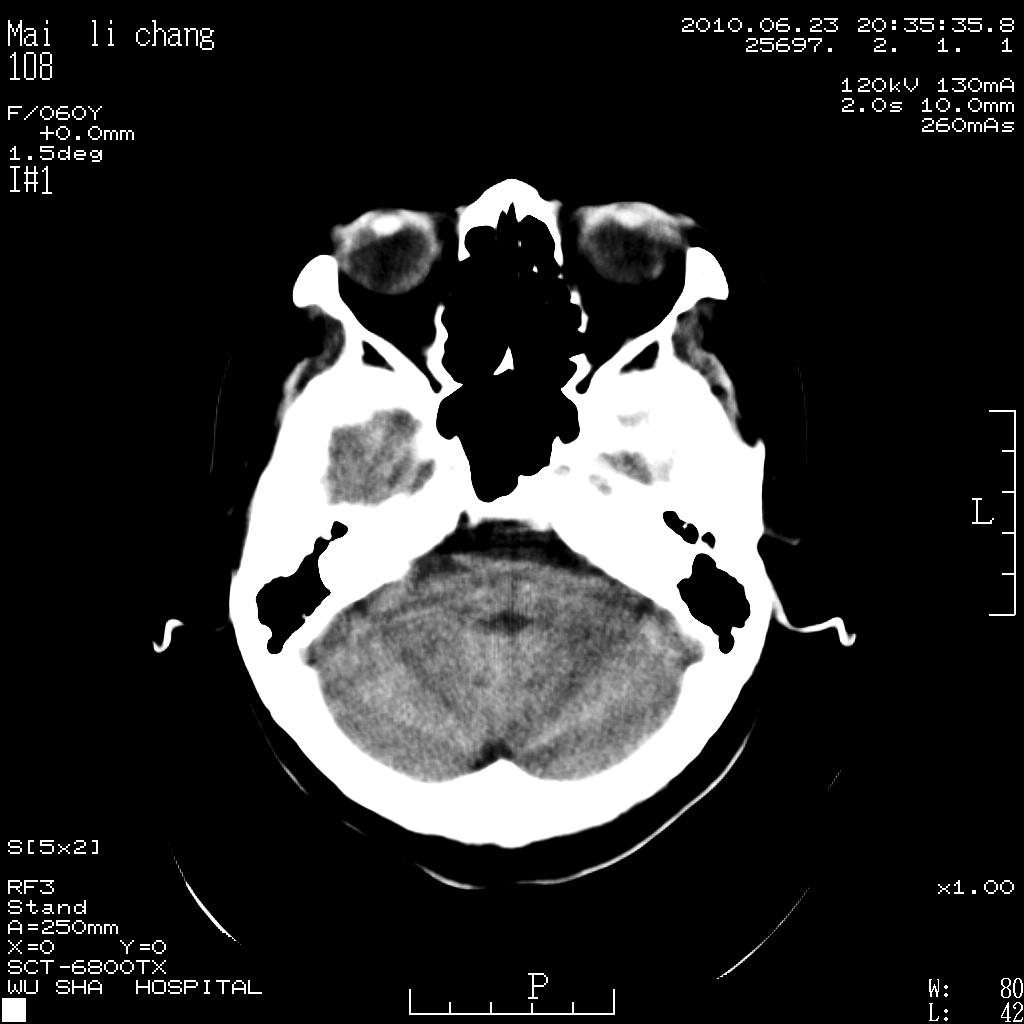

女性,60岁,右手无力一天

脑梗塞?并皮层下动脉硬化性脑病?还需要考虑什么?请大家指导,先谢了。

考虑左侧基底节区脑梗塞。

左侧基底节区及放射冠区多发脑梗塞。

左侧基底节区及侧脑室旁多发脑梗塞

1.病人60岁,右手无力一天。

2.左侧基底节区可见片状低密度病灶。

意见考虑脑梗塞。

左侧基底节区大面积梗塞,必要增强扫描协诊